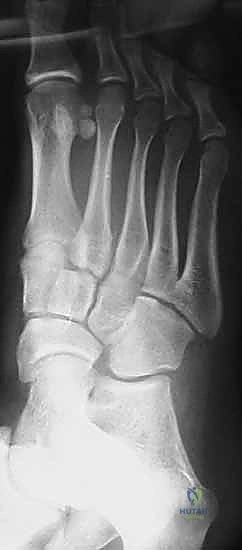

2. التصوير بالأشعة السينية (X-Rays) مع تحميل الوزن

الأشعة السينية العادية قد لا تظهر الإصابة إذا لم تكن العظام مزاحة بشكل كبير. السر يكمن في طلب أشعة سينية أثناء وقوف المريض وتحميل وزنه على القدم المصابة (Weight-bearing X-rays).

* يبحث الدكتور هطيف عن "علامة الفليك" (Fleck Sign)، وهي قطعة عظمية صغيرة مكسورة ومسحوبة من قاعدة المشط الثاني أو العظم المسماري الإنسي، وهي دليل قاطع على تمزق رباط ليزفرانك.

* كما يتم قياس المسافة بين قاعدة المشط الأول والمشط الثاني. أي اتساع يزيد عن 2 ملم يُعتبر غير طبيعي ويشير إلى عدم الاستقرار.